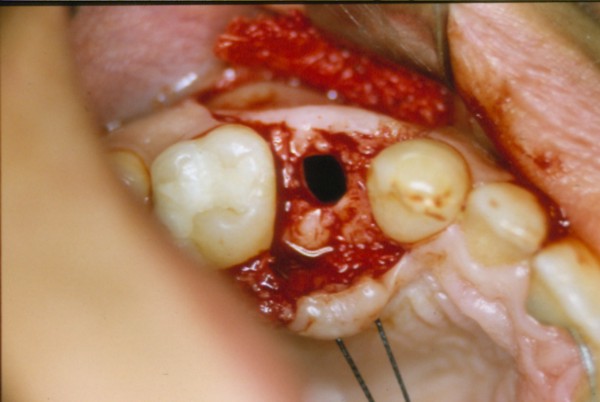

Nada más comenzar la insinuación del lecho implantario con la fresa lanceolada, ingresamos en una cavidad demasiado profunda que nos alarma y llama nuestra atención.

Agrandamos el diámetro de nuestra perforación, y observamos que carece su interior de fluidos sanguinolentos, purulentos o serosos, que puedan hacernos pensar en algún quiste residual, o entidad patológica alguna que pudiera haber pasado desapercibida a la observación clínica o radiográfica por omisión.(DIAPO 4)

Instalamos en su interior una galga de profundidad, ingresando esta en su totalidad.(DIAPO 5-6)

DIAPO 6

Estábamos en pleno Seno Maxilar.

(curiosamente, la maniobra de Valsava era negativa)

Se recetaron antibióticos de amplio espectro, lavajes por vía nasal de agua de mar, y las pertinentes recomendaciones post operatorias.

Dos meses después se instaló un puente ceramo metálico fijo convencional (DIAPO7).